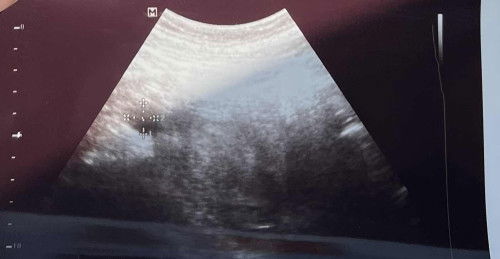

Hi semua…sy taktahu sy pregnant. Pg clinic sbb mual and perut cramp je. Ble buat upt, +ve.. doctor ckp kalau nak scan boleh. Dah scan xnampak apa dlm rahim lepastu doctor nampak mcm kantung luar rahim :( cuma doctor laki die xconfirm jugak tu apa benda. Dia bg surat suruh refer buat tvs.. Harap2 bukan ectopic sbb sy ttc :( so far xde bleeding, cuma cramp nk period je. Ada yg pengalaman scan rupa mcm ni jgk tak? Sy refer doctor satu lg dia ckp masih awal jgk nak ckp tu ectopic abb baruuu 4w. Cuma tertanya apa benda laaaa benda dlm tu 😭

UPDATE: its actually right ovary cyst. Alhamdulillah dalam rahim nampak kantung. Doctor ckp by time cyst tu akan mengecut. Now dah boleh lega sikit 🥲